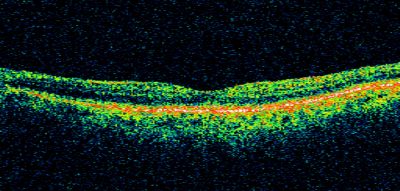

Wet AMD - Subfoveal CNVM - Excellent Response to Avastin

76-year-old woman two to three months of vision loss OD

Vision started at 20/200 and with Avastin improved to 20/25.  She has required monthly injections and as of October 2010 has been treated about 16 times.  Her left eye remains good at 20/20.

The OCT from post-treatment as well as pretreatment images are in this album.